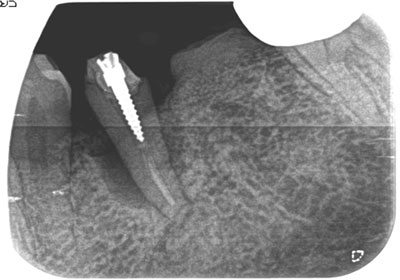

主訴 左下第二小臼歯の動揺、咬合痛の為来院。

まずはブラッシング指導を行い、プラークコントールが15%以下で、出血もなくなったことを確認。

その後、フラップオペ(歯肉を開く)をし、歯肉縁下の歯石を取り、歯周組織再生剤のリグロスを注入し、縫合。

約14ヶ月後には、遠心部の骨が再生され、硬線もクリアに見えてきている。

費用 8万 (オペ・歯周組織再生剤を含む)